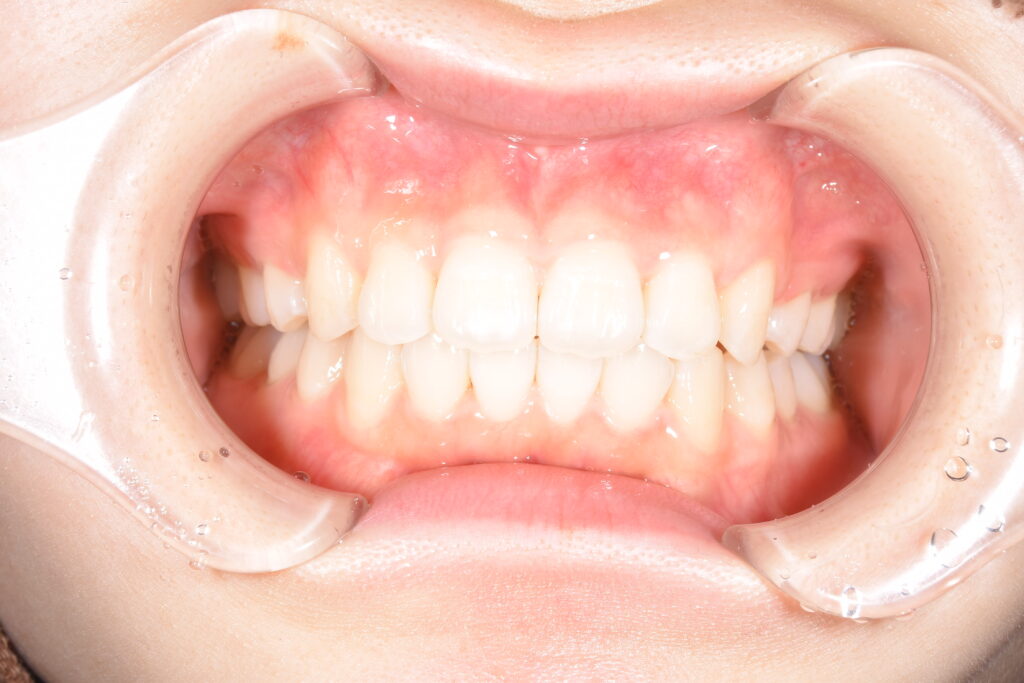

矯正開始1年6カ月後です。(治療終了時)

【治療終了時】

しっかり装着時間を厳守してもらえたおかげで、理想的な歯並びになりました(^^♪

患者様にもご満足して頂けました!

今回、治療を行うにあたって、抜歯2本を行いました。インビザラインでは、従来の針金矯正よりも抜歯を回避し治療を行えることがあります。ただ、今回の患者様はどうしても上の前歯を下げることが必要で、移動量も多かったため、患者様に説明の上、このような治療計画となりました。

よく、インビザラインでは抜歯矯正は無理だ、とのお話もちらほら耳にしますが、このように抜歯を行っても理想的な歯並びとすることができます(*^-^*)